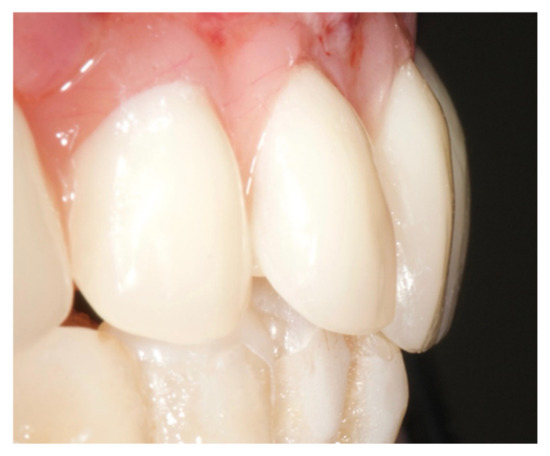

After implant insertion and teeth extraction, the multi-unit abutments were screwed (Figure 6), and an impression was taken to prepare a provisional screwed retained prosthesis.

The healing screws were screwed after 6 h, the provisional prosthesis was screwed, and an occlusal check was performed (Figure 7).

Figure 6. Multi-unit abutment were screwed on the implants after the surgery.

Figure 7. Provisional prosthesis was screwed, and the occlusal check was done.